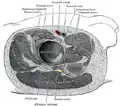

Querschnitt in Höhe des Hüftgelenks.

Querschnitt in Höhe des Hüftgelenks. -